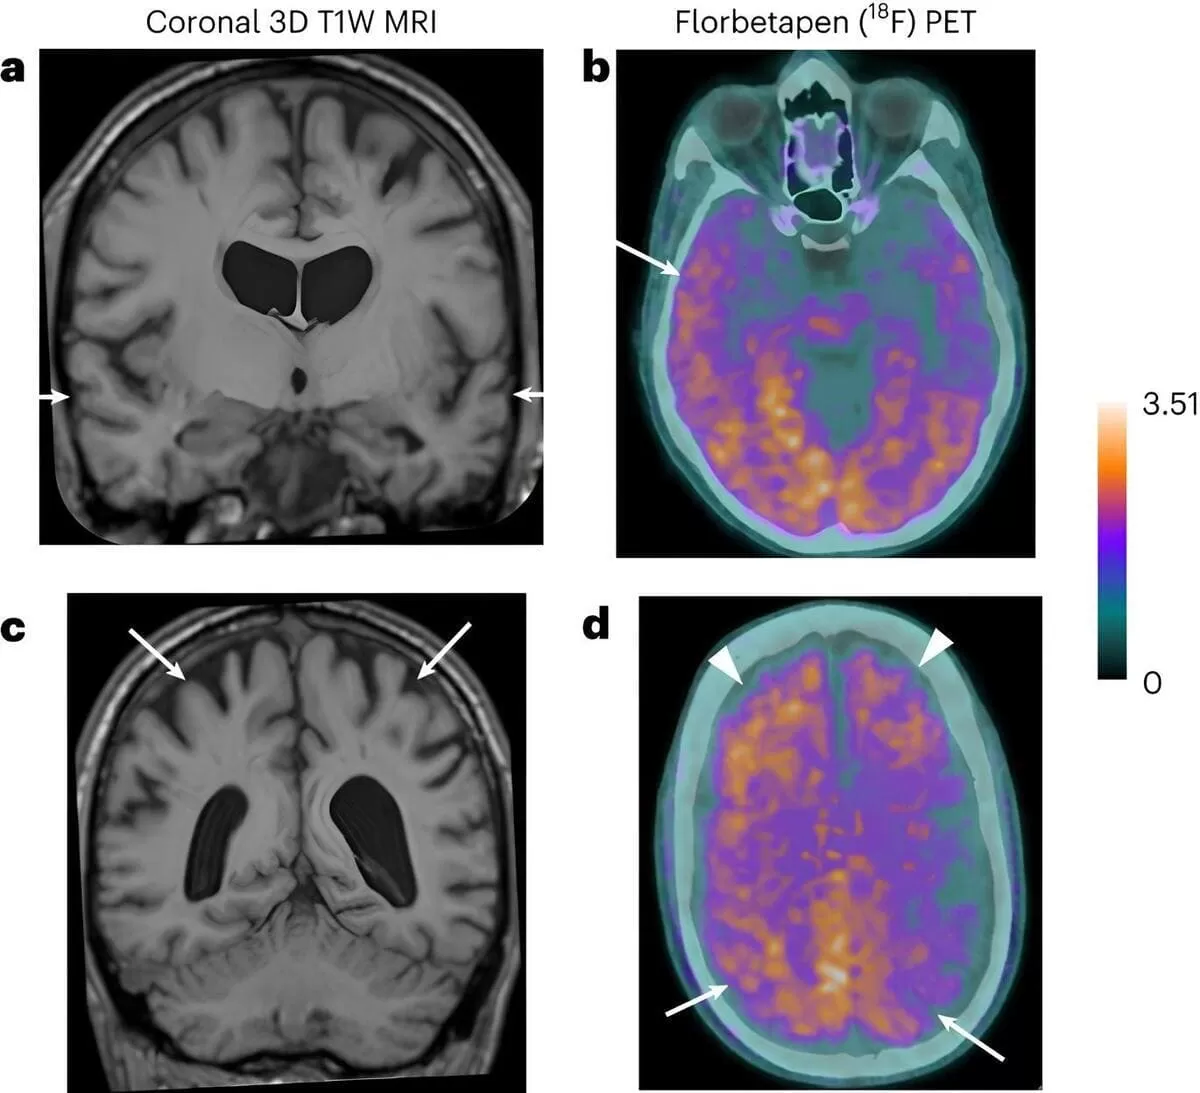

Estas personas tenían entre 38 y 55 años cuando empezaron a tener síntomas neurológicos. Los análisis de biomarcadores apoyaron los diagnósticos de alzhéimer en dos pacientes confirmados, y fue sugestivo en otra persona; un análisis de autopsia mostró patología de Alzheimer en otro paciente.